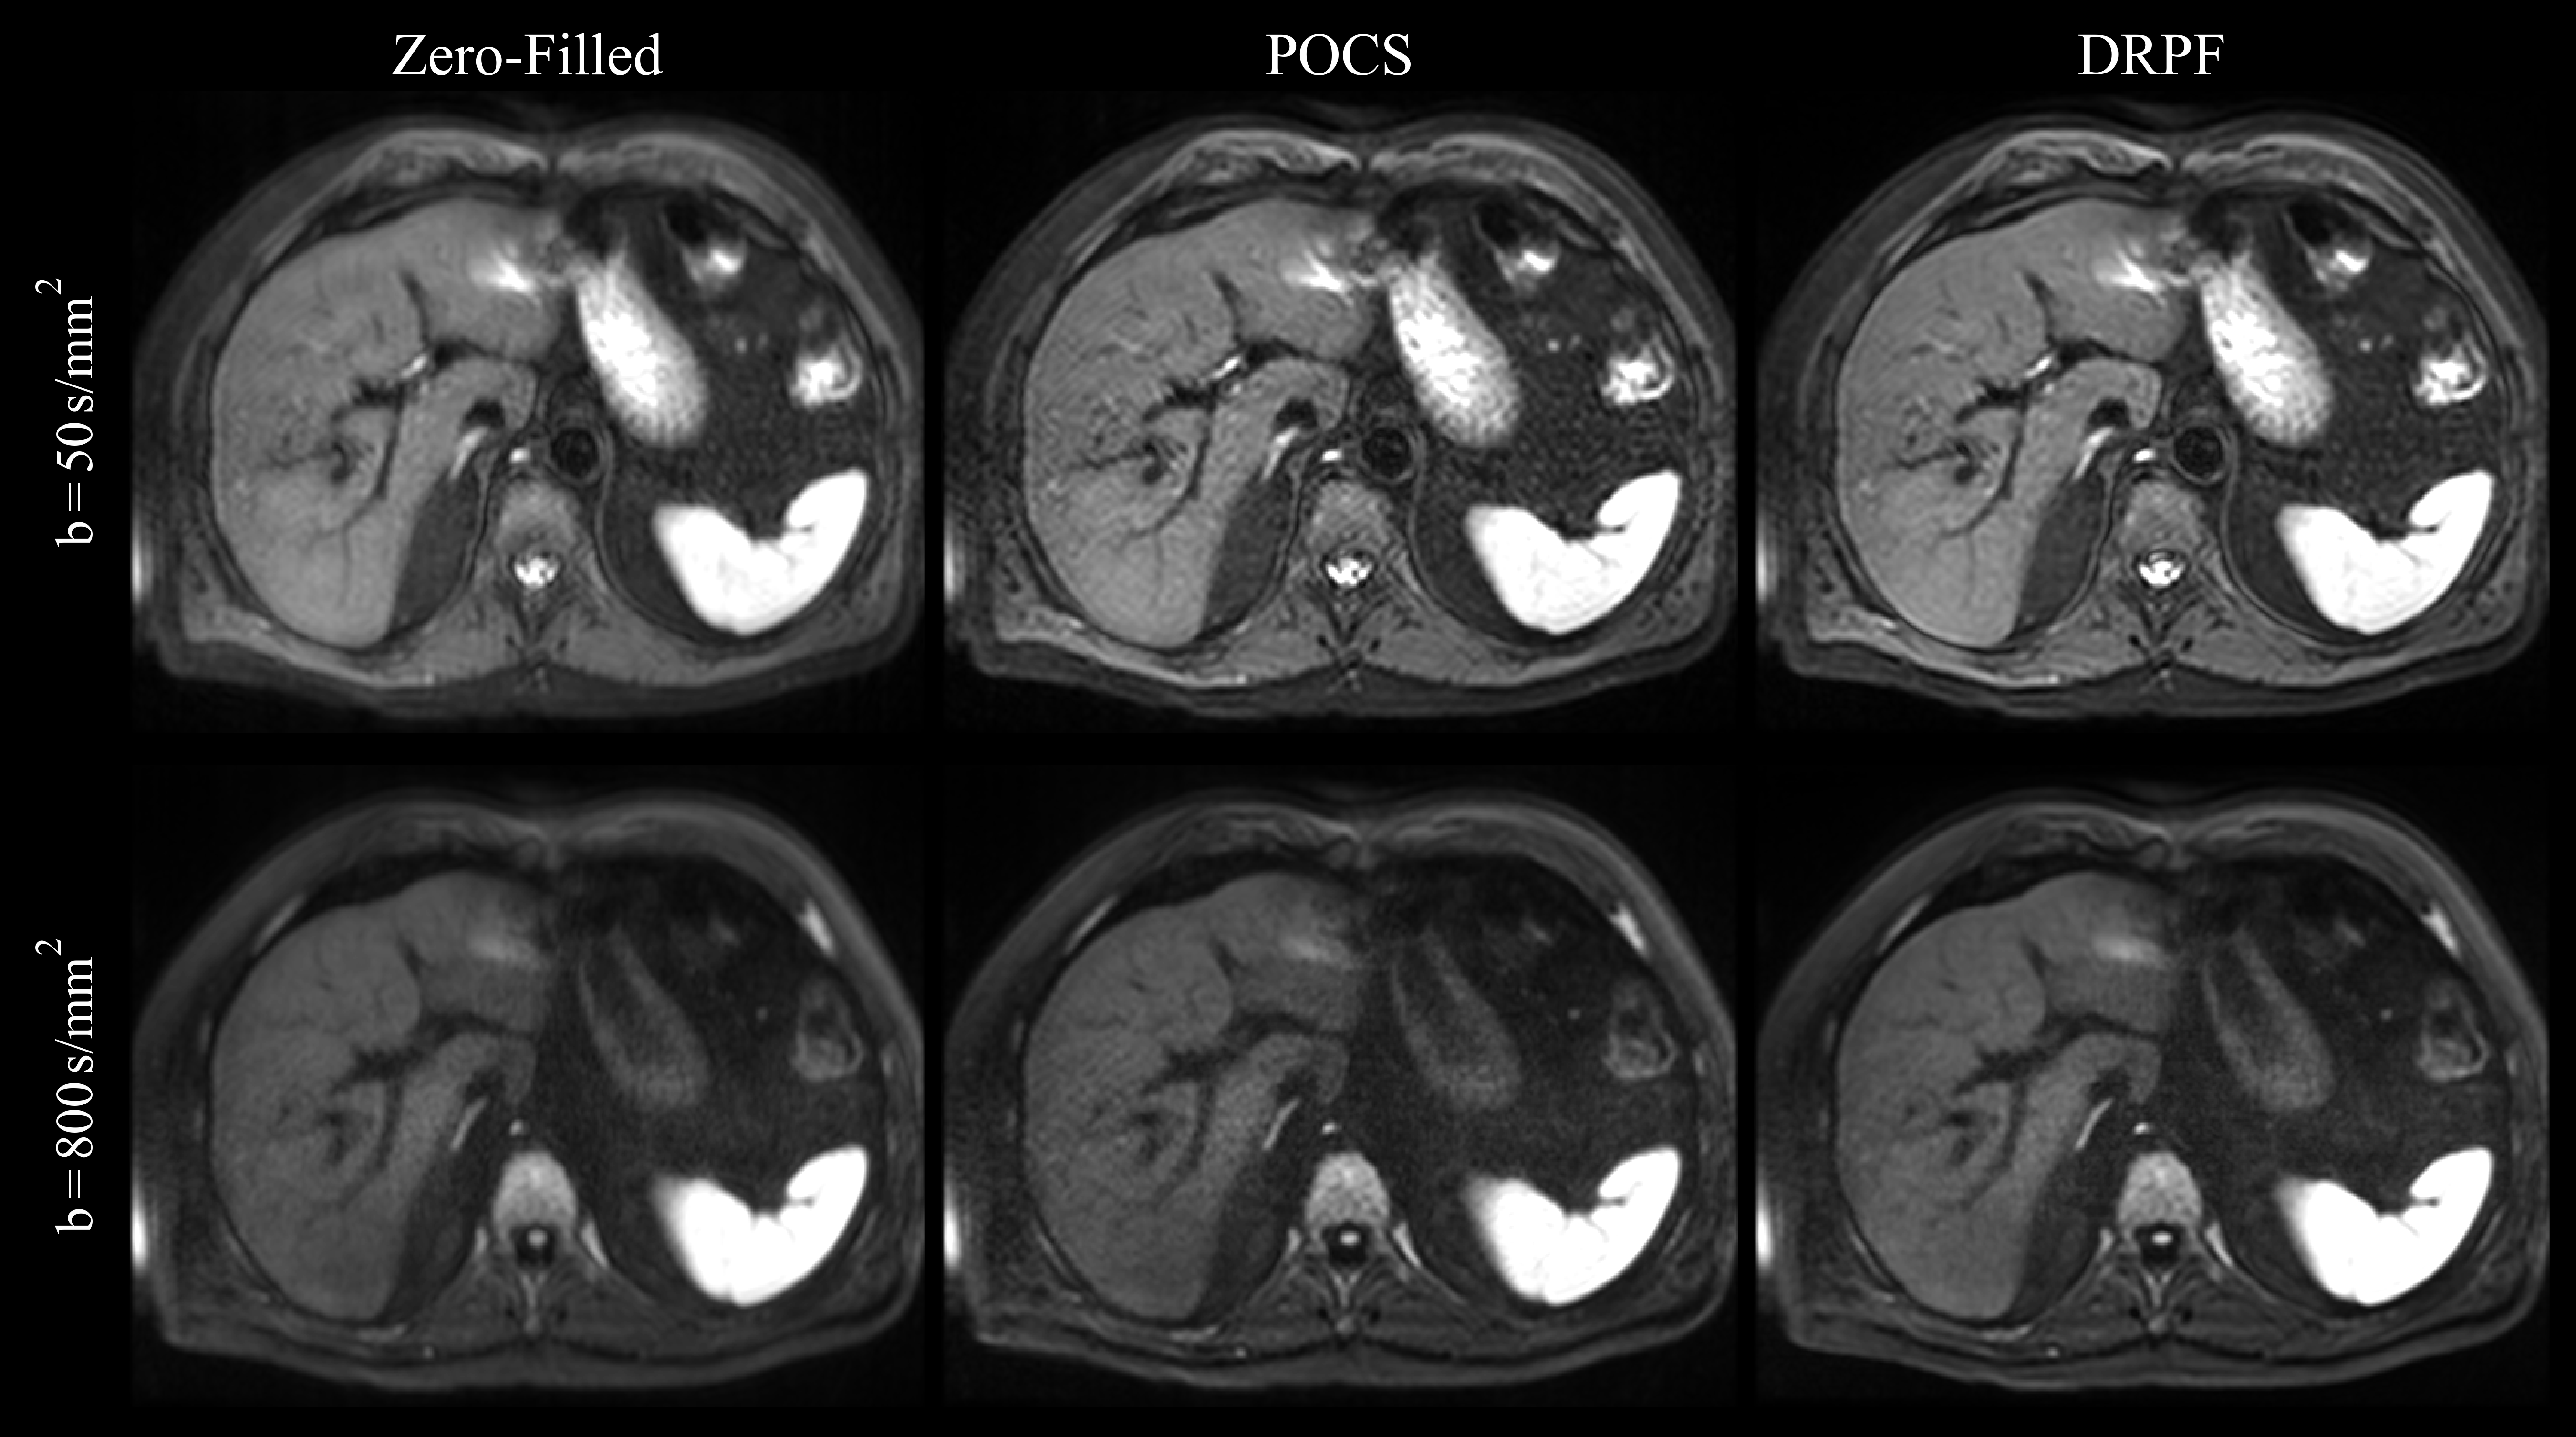

As demonstrated in Figure 5, the proposed method also performs well on prospectively sub-sampled data. Compared to the zero-filled reconstruction, DRPF is able to restore resolution along the sub-sampled direction for both b𝑏b-values. POCS reduces blurring as well but introduces additional noise and a mesh pattern. Representative reconstructions on prospective data of two additional subjects are presented in Supporting Information Figure S4.

Refer to caption

Figure 5: Qualitative evaluation of zero-filling, POCS and DRPF on a representative prospectively PF-sampled liver slice (PFF=5/8PFF58\text{PFF}=5/8, 1.5 T) acquired at b𝑏b-values of 50 s/mm2 (top row) and 800 s/mm2 (bottom row).